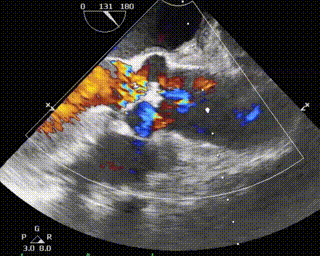

患者为68岁男性,因心悸胸闷入院。术前超声报告显示,患者为功能型二叶式主动脉瓣,右无融合钙化,主动脉瓣明显增厚钙化,瓣叶开放受限,主动脉瓣前向血流加速Vmax=4.2m/s,平均跨瓣压差36mmHg,有效开口面积0.7cm²,舒张期瓣口中度反流信号。

术前、术后超声对比

本次手术植入瓣膜定位准确,操作简便,症状即刻改善。术后超声显示瓣口未见明显反流,微量瓣周漏,主动脉瓣前向血流加速Vmax=1.9m/s,有效开口面积2.9cm²,PGmean=8mmHg。患者生命体征稳定,手术室当场清醒,手术圆满成功。术后复查超声恢复良好,3天后出院。